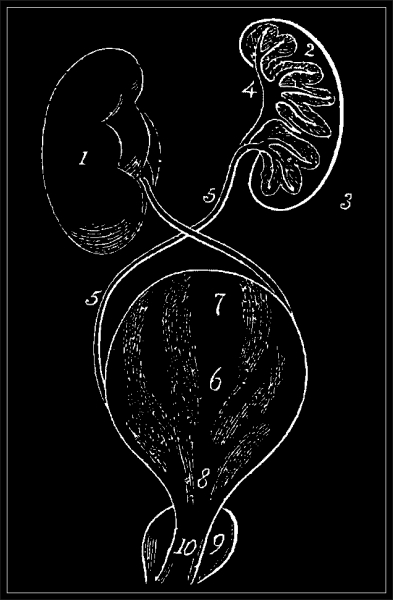

The annexed diagram will explain the coats and facilitate the understanding of subsequent descriptions.

1. Body of the Testicle.

2. Epididymis.

3. Vas Deferens.

4. Spermatic Artery.

5. Veins.

6. Cremaster Muscle

7. Tunica Albuginea.

8. Tunica Vaginalis.

9. Scrotum.

3, 4, 5, 6, and 8 constituting the Spermatic Chord.

View larger image

6. Cremaster Muscle.